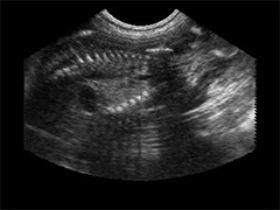

אבן בכיס מרה

כליה